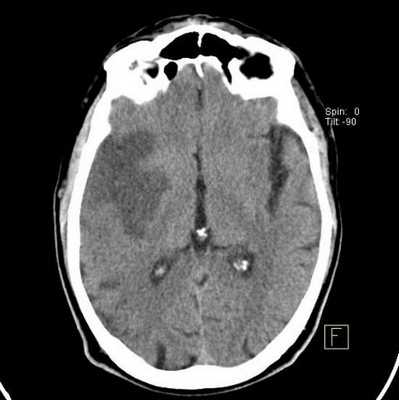

Ишемический инсульт (МР-сканирование)

Очаги ишемии головного мозга на МРТ

Нарушение кровотока в артериальном бассейне или незамкнутом Виллизиевом круге может сопровождаться формированием обширного участка ишемии. Зона повреждения на МРТ головы будет неправильной формы с нечеткими границами из-за отека. Поражение артерий мелкого калибра выглядит как лакунарный инфаркт (округлая локализованная область изменений).

При продвинутой стадии дисциркуляторной энцефалопатии острое нарушение мозгового кровообращения иногда протекает бессимптомно. Признаки инсульта выявляют только на МР-сканировании. Изменения видны на нативных снимках, контрастирование показано при подозрении на опухоль, вызвавшую ишемию, или энцефалит.